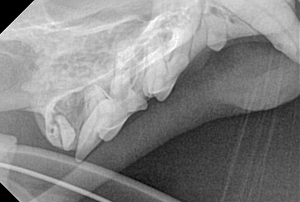

Canine Full Mouth Radiograph Example